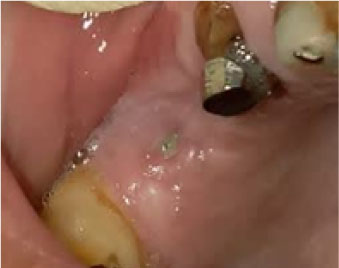

In terms of severity, Class I exposure was the most common with seven implants. Moreover, Class III was the least common with only one implant. The number of exposed maxillary and mandibular implants is presented in Figure 1. Also, Figures 2-6 show the exposure of maxillary premolar implants.

Figure 4. Class I exposure of a maxillary first premolar implant and Class II exposure of a maxillary canine implant.